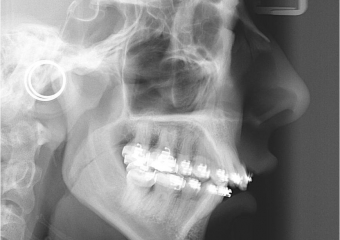

Telerradiografia inicial